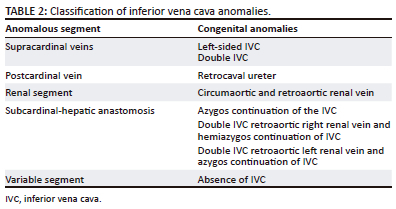

A double IVC has a left-sided IVC in addition to the normal right IVC. It results from persistence of both supracardinal veins. The left IVC crosses the midline anterior to the aorta to join the right IVC (Figure 2). There may be variations in calibre of the left and right IVC.1,9 The incidence of double IVC has been reported between 1% and 3%.15 Recurrent pulmonary embolism despite IVC filter placement should raise suspicion of a double IVC. Review of prior cross-sectional images before IVC filter placement is useful to diagnose congenital IVC abnormalities such as double IVC. If no prior cross-sectional images are available for review, cavography through the left iliac vein should be performed prior to filter placement. A filter can be placed into each cava if a double IVC is present. The aberrant vessel may also mimic a lymph node.1,7,9